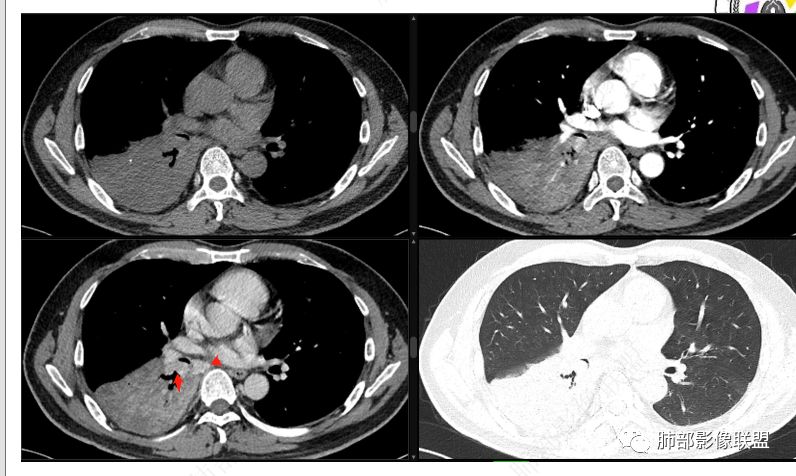

右肺下叶实变,周围磨玻璃,近端支气管扩张,管壁凹凸不平,远端阻塞,可见粘液栓,不均匀强化,有低密度无强化影,其内血管显示尚可,考虑粘液腺癌,鉴别淋巴瘤

右肺下叶大片实变,密度不均匀,可见支气管充气征及粘液区,右肺下叶支气管内结节影,下叶支气管阻塞,病灶前下可见磨玻璃影,右侧积液,考虑粘液腺癌,鉴别类癌?

右下叶支气管狹窄,内见高密度强化结节,远端大片不张实变,实变内可见多发粘液拴,整体观察实变似有见缝就针的感觉,综和分析考虑粘液表皮样癌,其次考虑类癌

中央型肿瘤pk周围型肿瘤  。壮年男性,热咳一周伴气喘,中性白细胞升高,临床是个感染过程。支持中央型病变的证据:1  肺门明显强化结节 2 横s征  3 支气管粘液栓  4 主支气管变窄,似见冰山征      支持周围型病变:1 按叶段塑形  2 血管造影征  3 病灶内弥漫高强化  4 周围伴磨玻璃灶,但境界不清继发感染?误吸?综合 中央型肿瘤可能大:类癌》鳞癌

右肺下叶不张,右下肺门区高强化结节,似乎呈冰山征,首先考虑类癌可能

右下肺门似见一结节影,明显强化,远端支气管黏液栓,右肺下叶不张,考虑类癌,次之黏液表皮样癌 腺样囊腺癌

右肺下叶支气管见结节灶继发右肺下叶膨胀不全,右肺中央局部炎性改变,下叶支气管结节动脉期明星强化,静脉期强化减低,首先考虑肺鳞癌,鉴别类癌、粘液表皮样癌。